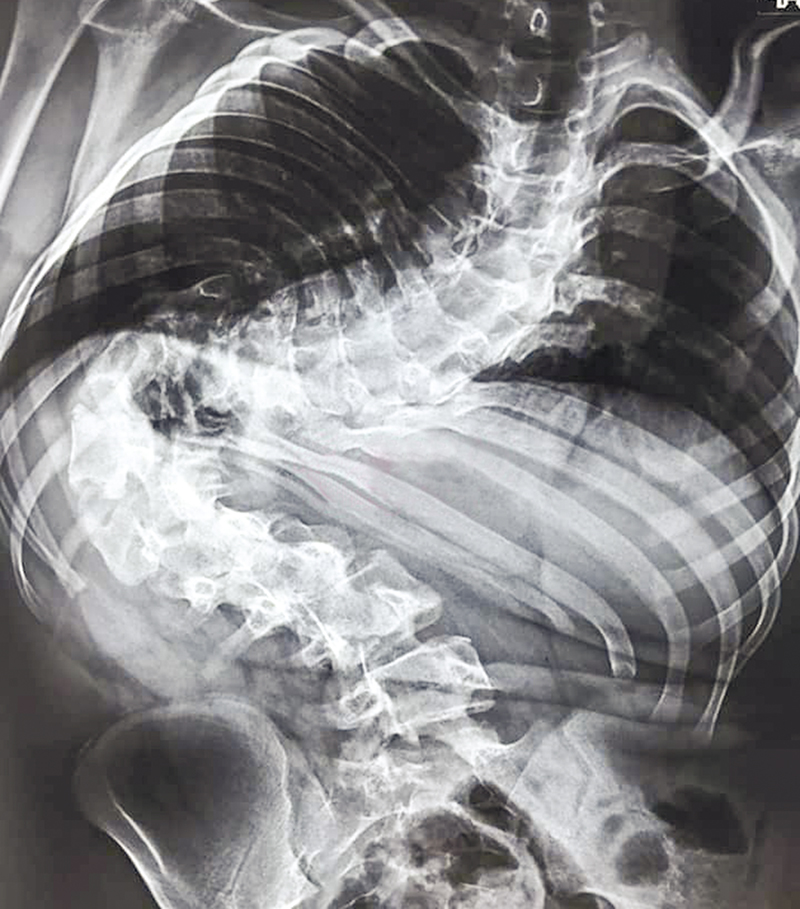

Matheus Lima de Oliveira, 16 anos, recebeu alta do hospital na quarta-feira, 7, após fazer cirurgia complexa com duração de 10 horas, no dia 26 de julho, para correção de escoliose com um desvio de 142 graus da coluna. A operação só foi possível devido decisão do Juízo da Vara Cível da Comarca de Senador Guiomard, que bloqueou o valor necessário para custeio da cirurgia, realizada em unidade hospitalar particular, em São Paulo.